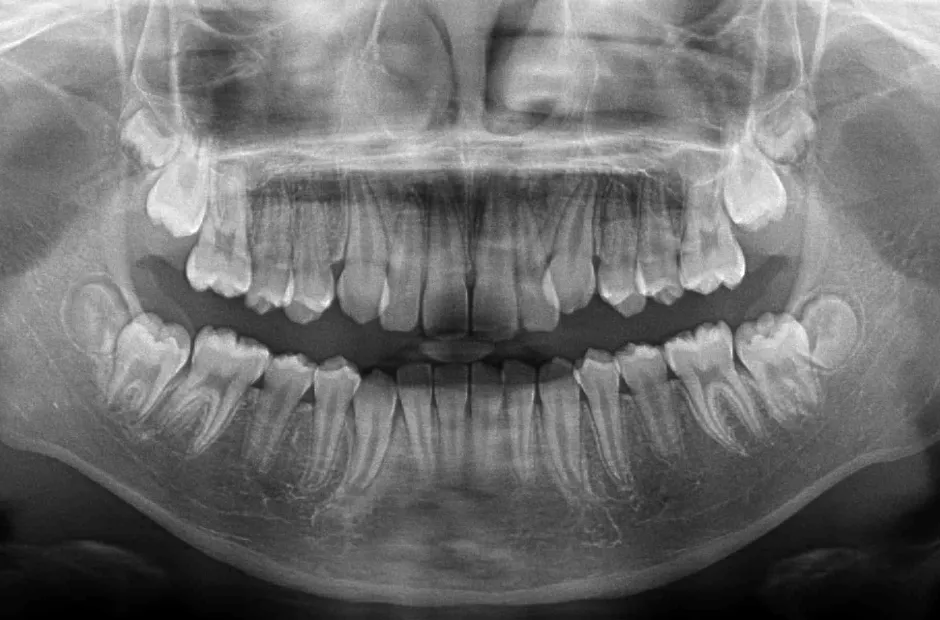

口腔内写真やレントゲンの撮影、歯型取りなど、口や顎の状態を詳しく把握するための精密検査を行ないます。さらに、骨の成長状況や身長・体重の増加傾向、永久歯の生えかわりについても確認します。

治療症例

ブラケット矯正

前歯部反対咬合

| 診断名・主訴 | 前歯部反対咬合 |

|---|---|

| 年齢・性別 | 14歳・男性 |

| 治療期間・回数 | 1年2か月 |

| 治療に用いた主な装置 | ブラケット矯正 |

| 抜歯部位 | なし |

| 治療費 | 60万円(税抜) |

| リスク・副作用 | 装置による違和感・疼痛・歯肉退縮・歯根吸収・虫歯のリスクなど |

治療前

治療後